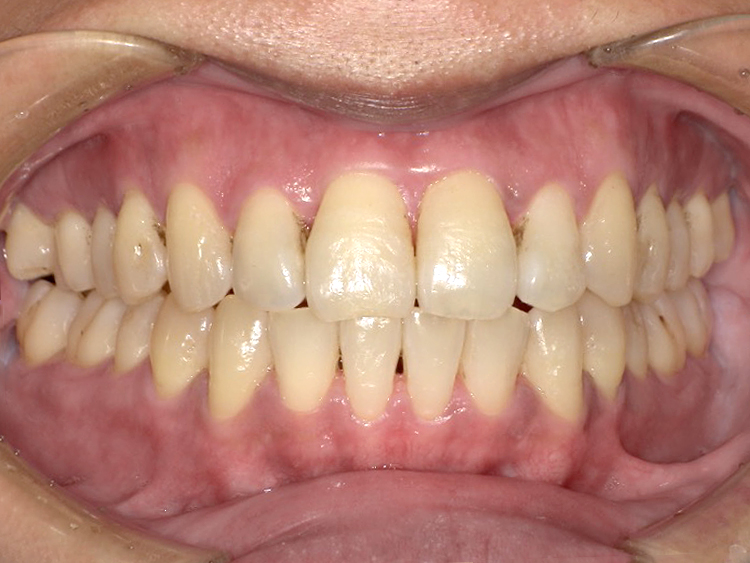

症例6

Before

After

| 主訴 | 噛み合わせが気になる |

|---|---|

| 年齢 | --- |

| 治療 期間 |

約2年11ヶ月 |

| 治療 内容 |

インビザラインコンプリヘンシブ 右上6番・左上6番ALLセラミッククラウン |

| 治療費 | ¥1,116,000(税込)/調整料含む |

| 治療のリスク | 歯を動かすことで、歯茎が下がるリスクある。 矯正終了後は、リテーナーを使用し、後戻りを防ぐ必要がある。 |